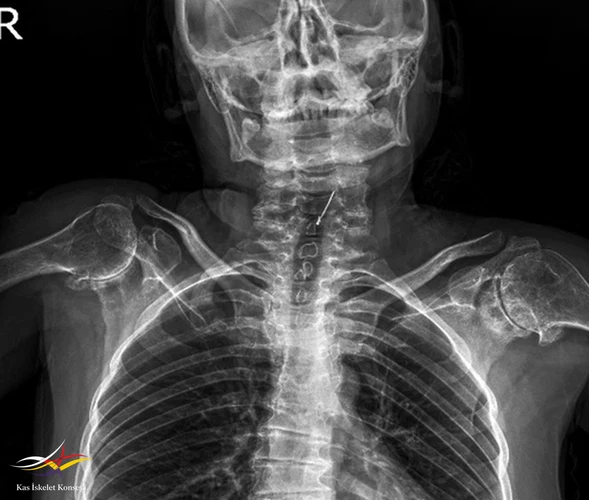

Resim 4.

Hikayesinden 5 yaşında coxa vara nedenli diz operasyonu (3 kez tekrar edilmiş), yaşını hatırlayamadığı bacak boyu uzatma operasyonu (çocukluk döneminde), 11 yaşında omuz cerrahisi (etyoloji aydınlatılamadı), 32 yaşında sağ kalça protez operasyonu öyküsü var.

Muayene: Fizik muayenede omuz, el bilek,dirsek, kalça, ayak bilek rom kısıtlı. El PIF'lerde şişlik, büyümüş kemiksi eklem görünümü? Boy kısa, kifotik görünüm mevcut? Artrit yok, ateş, kilo kaybı,oral aft genital ülser, ağız göz kuruluğu, Raynauld fenomeni yok.

- Klinik Özellikler: Kısa boy-kısa gövde: Özellikle ergenlik öncesi veya ergenlik döneminde gelişir. Gövde kısalığı ve fıçı göğsü belirgin olabilir. Her iki kol uzunluğu boy uzunluğundan fazla olur

3. Ek bulgular: Omurga büyümesi normal doğumdan sonra başlar, ancak ergenlik öncesinde yavaşlar.